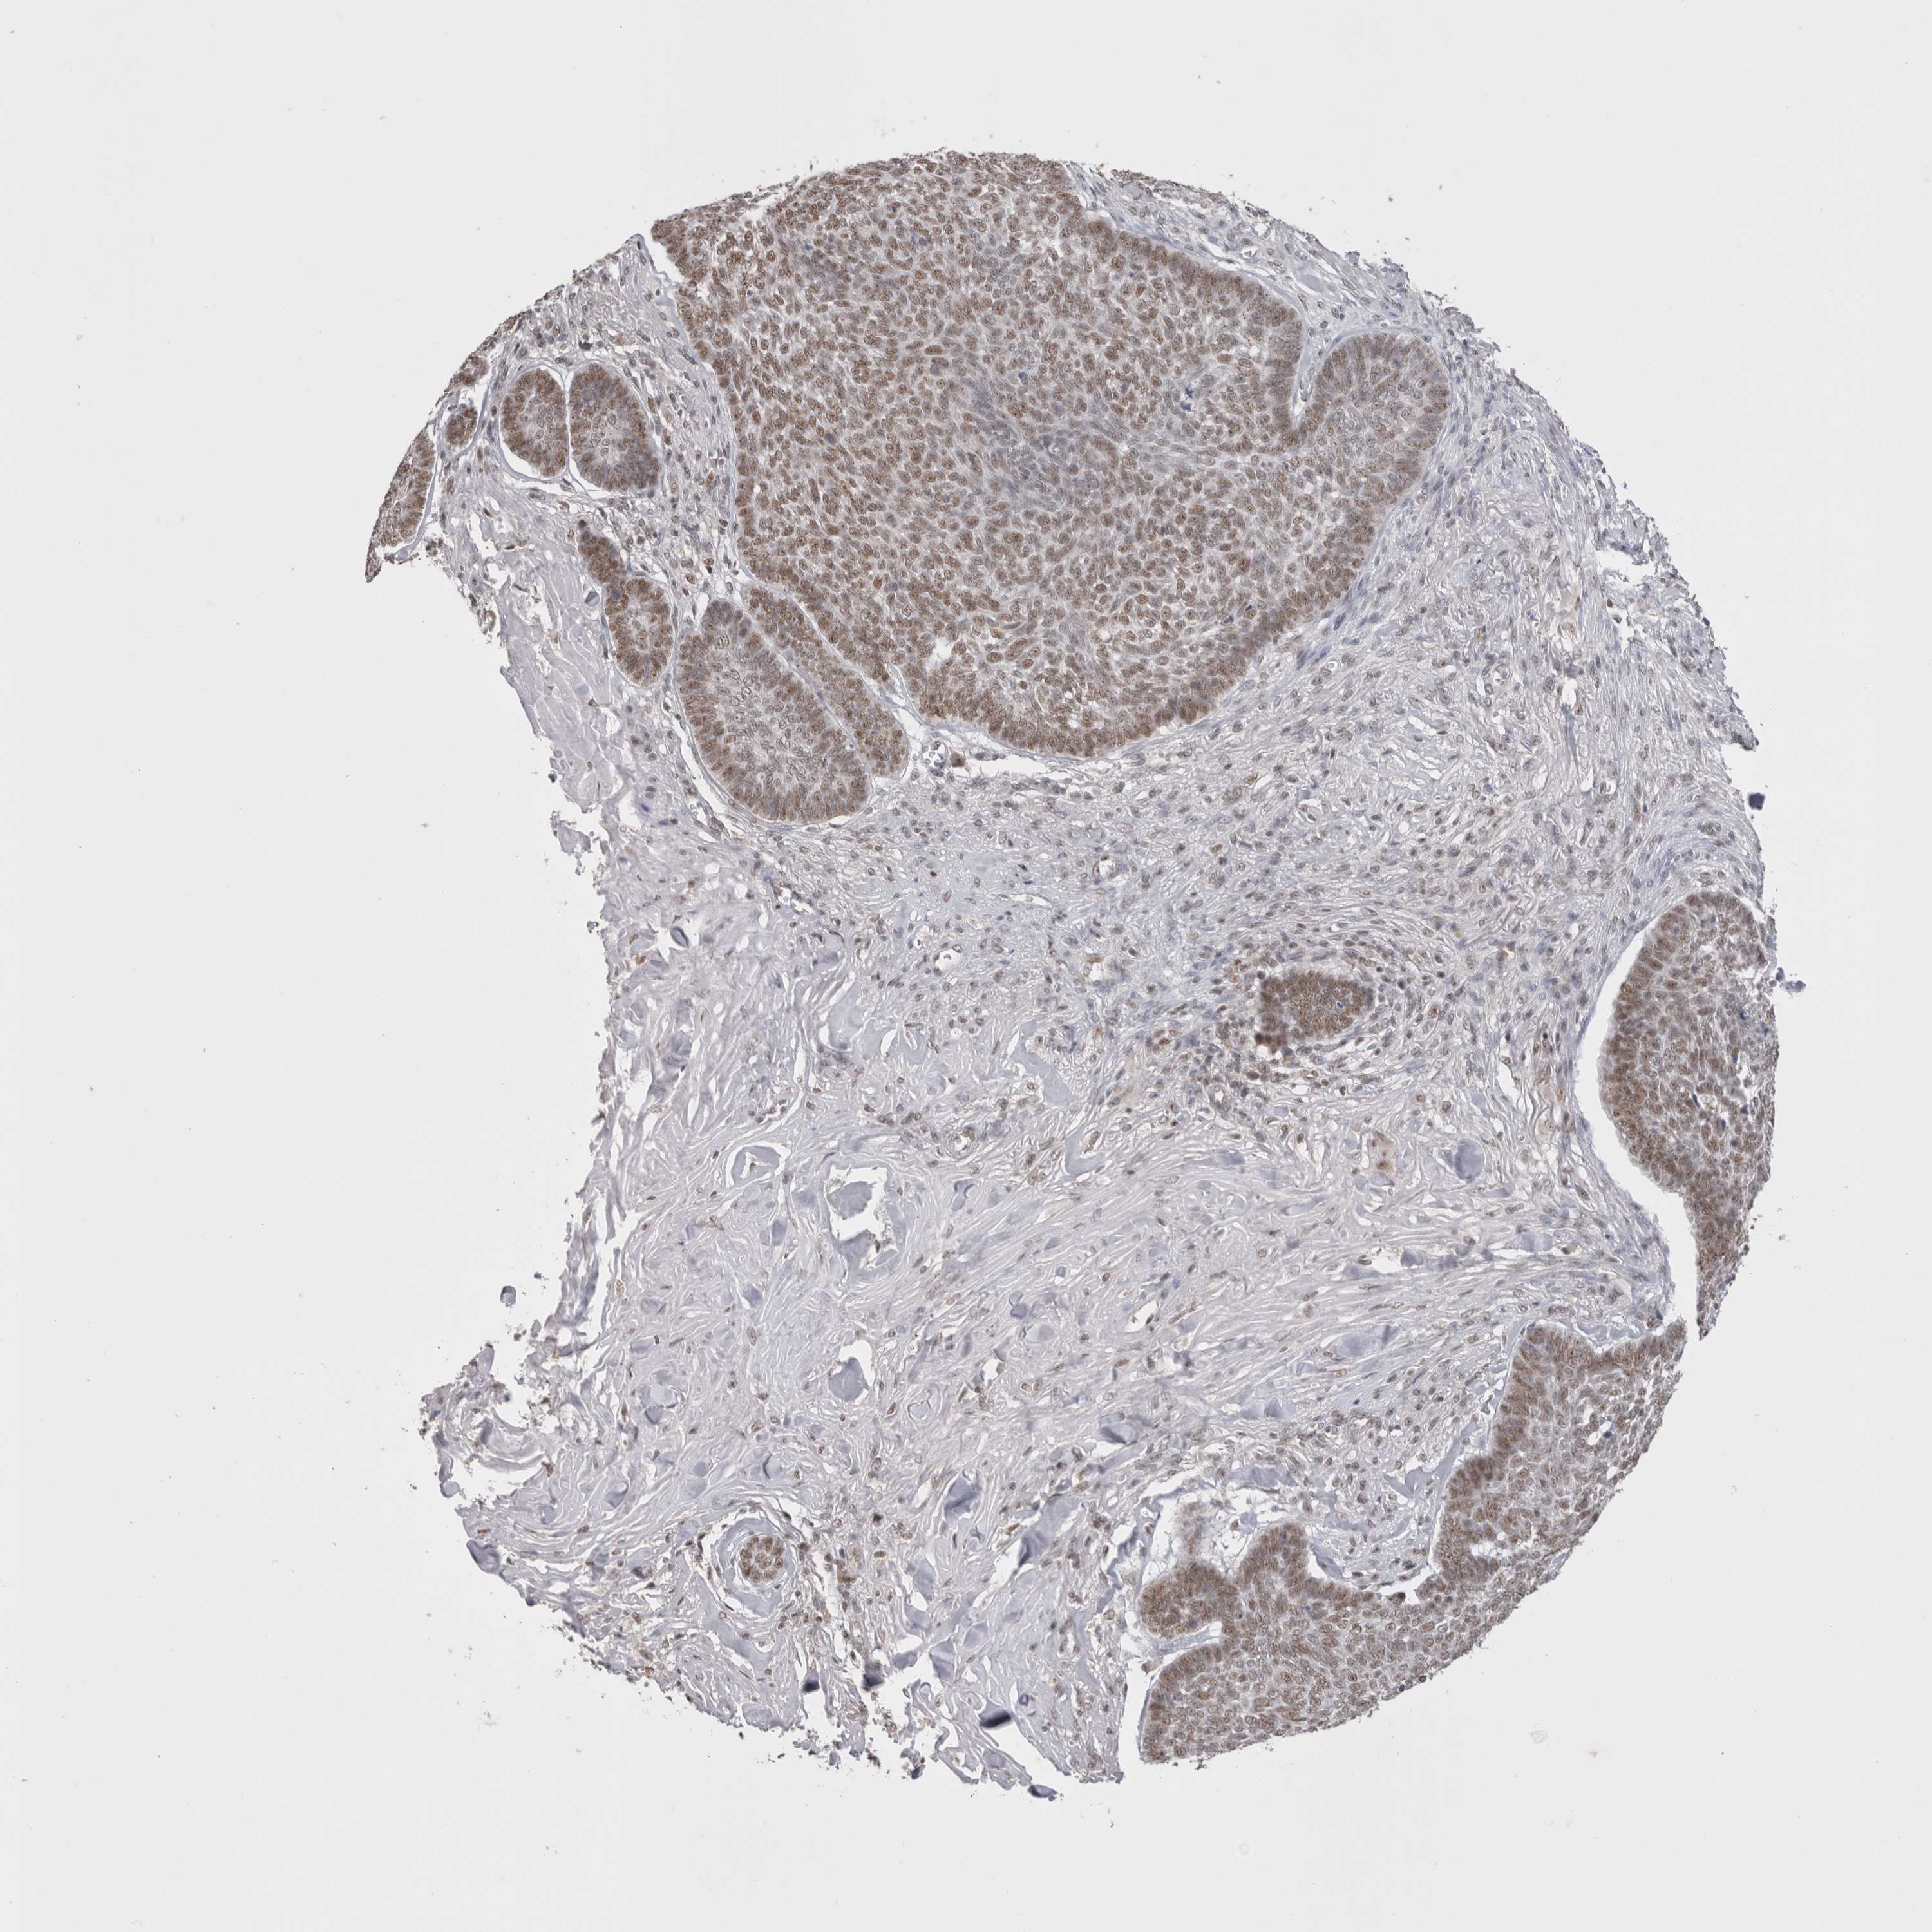

SKIN CANCER - Protein expressioni

A mouse-over function shows sample information and annotation data. Click on an image to view it in a full screen mode. Samples can be filtered based on level of antibody staining by selecting one or several of the following categories: high, medium, low and not detected. The assay and annotation is described here.

Antibody stainingi

Antibody staining in the annotated cell types in the current human tissue is reported as not detected, low, medium, or high, based on conventional immunohistochemistry profiling in selected tissues. This score is based on the combination of the staining intensity and fraction of stained cells.

Each image is clickable and will lead to virtual microscopy that enables deeper exploration of all samples and also displays staining intensity scores, fraction scores and subcellular localization as well as patient and tissue information for each sample.

Antibody HPA008736

Antibody CAB002224

Antibody CAB025546

Staining

High

Medium

Low

Not detected

Squamous cell carcinoma, NOS

Basal cell carcinoma

Adnexal tumor, benign